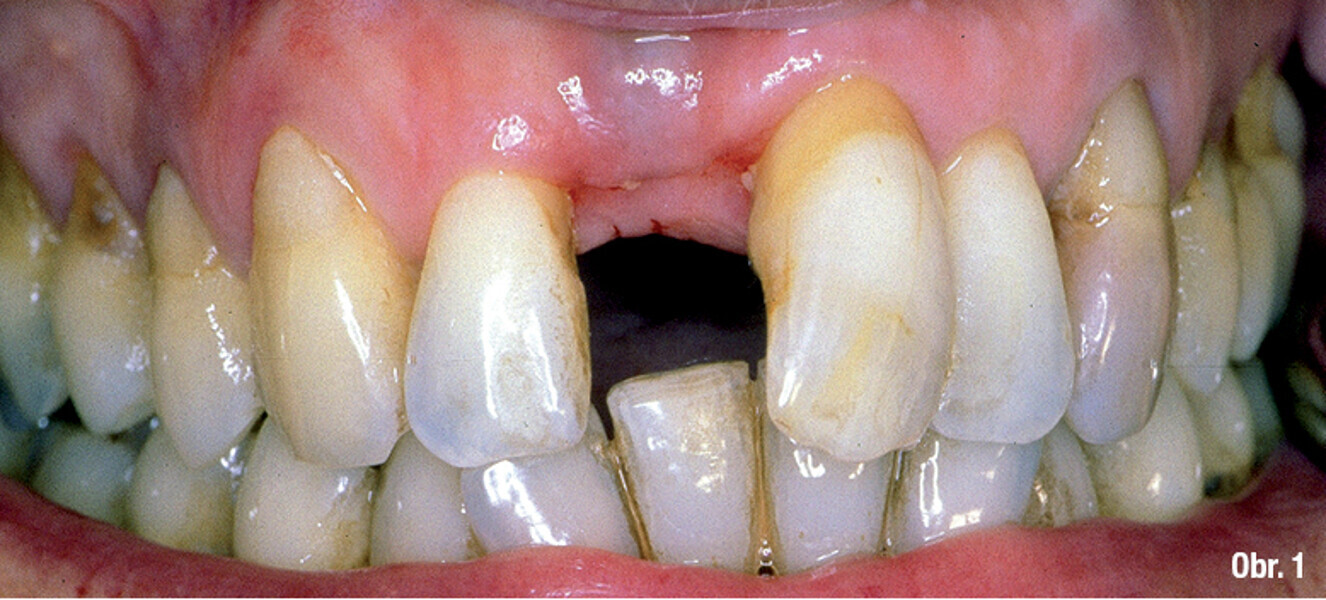

Triumfy a tragédie v implantologii